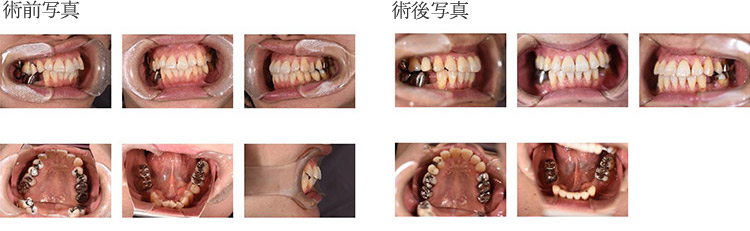

з—ҮдҫӢ5

зҹҜжӯЈжІ»зҷӮгӮ’еёҢжңӣгҒ•гӮҢжқҘйҷўгҖӮ

жӯҜгҒ®ж¬ жҗҚгӮ’иҖғж…®гҒ—гҒҰгӮӨгғігғ—гғ©гғігғҲжІ»зҷӮгӮӮеёҢжңӣгҒ•гӮҢгҒҹгҒҹгӮҒ

зҹҜжӯЈжӯҜ科治зҷӮеҫҢгҒ«гӮӨгғігғ—гғ©гғігғҲеҹӢе…ҘгӮ’иЎҢгҒЈгҒҹз—ҮдҫӢ

зҹҜжӯЈжІ»зҷӮ

гӮӨгғігғ—гғ©гғігғҲжІ»зҷӮ

| в‘ жІ»зҷӮеҗҚ | зҹҜжӯЈжІ»зҷӮеҫҢгҖҒж¬ жҗҚйғЁгҒҠгӮҲгҒіжӯҜж №зҠ¶ж…ӢгҒ®дёҚиүҜгҒӘжӯҜгӮ’жҠңжӯҜгҒ—гҒҹйғЁдҪҚгҒ«гӮӨгғігғ—гғ©гғігғҲгӮ’еҗҢжҷӮгҒ«еҹӢе…ҘгҒ—гҒҹз—ҮдҫӢ |

|---|---|

| в‘ЎиІ»з”Ё | гӮёгғ«гӮігғӢгӮўгҒ«гӮҲгӮӢжӯҜеҶ дҝ®еҫ©пјҲгӮөгғјгӮёгӮ«гғ«гӮ¬гӮӨгғүдҪҝз”Ёпјүпј“пј•дёҮеҶҶ/жң¬ |

| в‘ўжңҹй–“ | зҹҜжӯЈжІ»зҷӮгҒ«зҙ„2е№ҙ3гҒӢжңҲгҖҒгҒқгҒ®еҫҢгҖҖзҹҜжӯЈеҷЁе…·гҒ®ж’ӨеҺ»гӮ’иЎҢгҒ„дёЎеҒҙгҒ®гӮӨгғігғ—гғ©гғігғҲеҹӢе…ҘиЎ“гӮ’иЎҢгҒЈгҒҹгҖӮ |

| в‘ЈйҖҡйҷўй »еәҰ | гӮӘгғҡеҫҢгҒҜзҝҢж—ҘгҒ«жҙ—жө„гҖӮпј‘йҖұй–“еҫҢиҰіеҜҹгҖҒпј“гҒӢжңҲзөҢйҒҺиҰіеҜҹгҒ®еҫҢгҖҖеҚ°иұЎгҖҒи©ҰйҒ©гҖҒгӮ№гӮҜгғӘгғҘгғјеӣәе®ҡгҒ«гҒҰгӮёгғ«гӮігғӢгӮўгҒ®дёҠйғЁж§ӢйҖ гӮ’иЈ…зқҖгҒ—гҒҹгҖӮ |

| в‘ӨжӮЈиҖ… | пј•пј”жӯігҖҖеҘіжҖ§ |

| в‘ҘжІ»зҷӮеҶ…е®№ | е…ЁйЎҺжІ»зҷӮгӮ’зҹҜжӯЈжІ»зҷӮгҒ«гӮҲгӮҠгҒҫгҒҡиЎҢгҒЈгҒҹгҖӮдёӢйЎҺеҸіеҒҙпј•з•ӘгҒҜж¬ жҗҚгҒ—гҒҰгҒ„гҒҹгҖӮе·ҰеҒҙпј•з•ӘгҒҜжӯҜж №зҠ¶ж…ӢгҒҢжҘөз«ҜгҒ«гӮҲгҒҸгҒӘгҒҸзҹҜжӯЈжІ»зҷӮдёӯгҒ«жҠңжӯҜгӮ’гҒҠгҒ“гҒӘгҒЈгҒҹгҖӮ |

| в‘ҰжІ»зҷӮзөҗжһң | еҜ©зҫҺзҡ„гҒ«гӮӮжӮЈиҖ…ж§ҳгҒ®жәҖи¶ігӮ’еҫ—гӮүгӮҢгҒҹ |

| ⑧注ж„ҸзӮ№ | дёЎеҒҙгҒ®дёӯй–“ж¬ жҗҚгҒ®гҒҹгӮҒгҖҖгҒҫгҒҹзҹҜжӯЈжІ»зҷӮеҫҢгҒЁгҒ„гҒҶгҒ“гҒЁгӮӮгҒӮгӮҠжӯҜж №гҒ®е№іиЎҢжҖ§гҒ«гҒҜзү№гҒ«жіЁж„ҸгӮ’гҒҜгӮүгҒЈгҒҹгҖӮгҒқгҒ®гҒҹгӮҒжүӢиЎ“жҷӮй–“зҹӯзё®гҒ®иҰӢең°гҒӢгӮүгӮӮгӮөгғјгӮёгӮ«гғ«гӮ¬гӮӨгғүгҒ«гҒҰгӮӘгғҡгӮ’иЎҢгҒҶгҒ“гҒЁгҒҢеҰҘеҪ“гҒЁиҖғгҒҲгӮүгӮҢгҒҹгҖӮ |